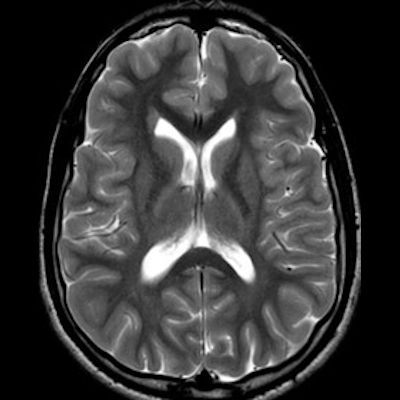

11 ay, Nöbet

Charlevoix-Saguenay Otozomal Resesif Spastik Ataksisi (ARSACS)

ARSACS (Charlevoix-Saguenay otozomal resesif spastik ataksisi) Sendromu

ARSACS

Autosomal recessive spastic ataxia of Charlevoix-Saguenay

Serebellar folya sinapsisi